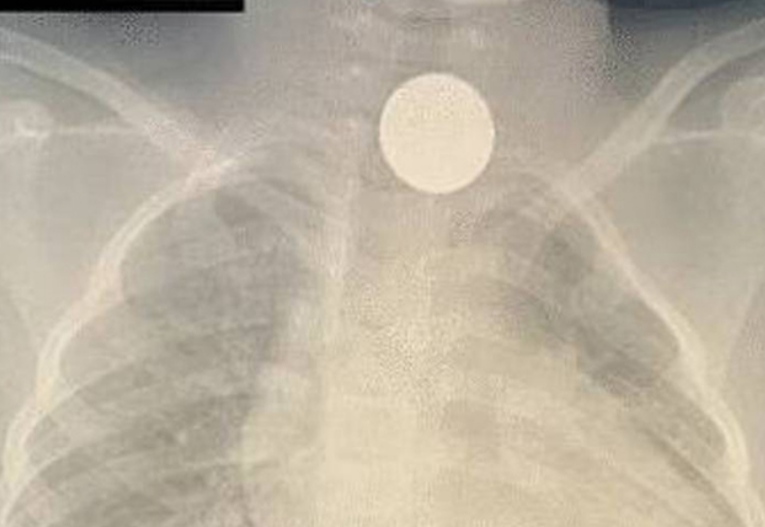

ಸ್ಥಳೀಯ ಮಾಧ್ಯಮಗಳ ಪ್ರಕಾರ, ಕಳೆದ ಎರಡು ವರ್ಷಗಳಲ್ಲಿ ಹಲವಾರು ಬಾರಿ ಆಸ್ಪತ್ರೆಗೆ ಭೇಟಿ ನೀಡಿದರೂ ಹುಡುಗಿಗೆ ಯಾವುದೇ ರೋಗಲಕ್ಷಣಗಳು ಅಥವಾ ಉಸಿರಾಟದ ತೊಂದರೆ ಇರಲಿಲ್ಲ. ನಾಲ್ಕು ವರ್ಷಗಳ ಹಿಂದೆ ಸಾಮಾನ್ಯ ಪರೀಕ್ಷೆಯಲ್ಲಿ ಬಾಲಕಿಗೆ ನಡೆಸಿದ ಎದೆಯ ಎಕ್ಸ್-ರೇಯಲ್ಲಿ ನಾಣ್ಯ ಕಾಣಿಸಿಕೊಂಡಿದೆ ಎಂದು ವೈದ್ಯರು ವಿವರಿಸಿದರು.

ನಾಣ್ಯವಿದೆ ಎಂದು ದೃಢಪಡಿಸಿದ ನಂತರ, ಎಲ್ಲಾ ವೈದ್ಯಕೀಯ ಪರೀಕ್ಷೆಗಳನ್ನು ನಡೆಸಿದ ನಂತರ ಹುಡುಗಿಯನ್ನು ಆಪರೇಷನ್ ಕೋಣೆಗೆ ವರ್ಗಾಯಿಸಲಾಯಿತು. ಬಳಿಕ ಸೂಕ್ಷ್ಮ ಪ್ರಕ್ರಿಯೆಯಲ್ಲಿ ನಾಣ್ಯವನ್ನು ಹೊರತೆಗೆಯಲು ಕುತ್ತಿಗೆಯ ಪ್ರದೇಶದಲ್ಲಿ ಛೇದನವನ್ನು ಮಾಡಲು ಶಸ್ತ್ರಚಿಕಿತ್ಸಕರು ನಿರ್ಧರಿಸಿದರು. ಇದೀಗ ನಾಣ್ಯ ಹೊರ ತೆಗೆದ ಬಳಿಕ ಬಾಲಕಿ ಆರೋಗ್ಯವಾಗಿದ್ದಾಳೆ.